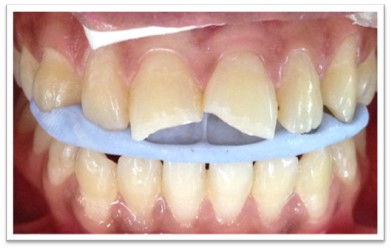

Patient Name:Padma Harkar

Tooth Involved : 11 12 13 21 22 23

Diagnosis : Fluorosis

Treatment : Direct Composite Veneers

Restoration: Direct Composite Using Nanohybrid composite

Stains masked using IVOCLAR EMPRESS COLOUR White And Honey.